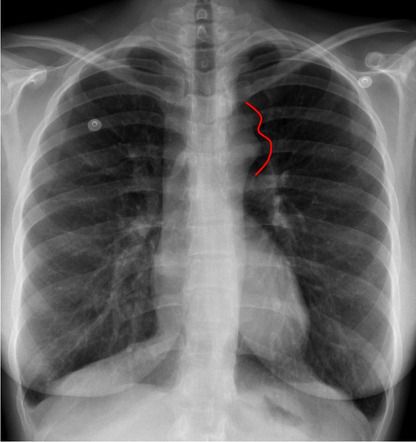

"Figure 3" sign on CXR in a patient with coarctation of aorta

Coarctation Of The Aorta

Figure3 Sign